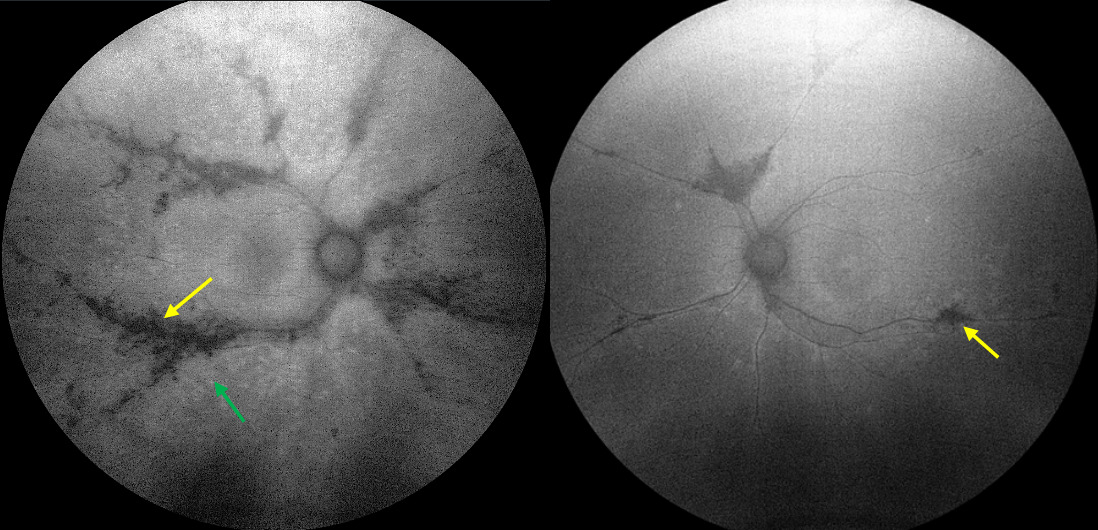

Fundus autofluorescence: Though the asymmetric presentation of the retinal findings was evident on white light fundus view (Figure 1), fundus autofluorescence was able to further highlight the marked difference between the two eyes. Figure 2 shows clear perivenous areas of geographic hypofluorescence (yellow arrows), which signify areas of retinal pigmented epithelium loss correlating with the pigment but that extend past the pigment noted on fundus examination. Additionally, subtle surrounding regions of hyperfluorescence at the edges of these hypofluorescent zones indicate areas of lipofuscin accumulation and retinal pigmented epithelium dysfunction (green arrow), proposing areas prone for future retinal atrophy. As such, fundus autofluorescence is a useful tool in monitoring patients with pigmented paravenous retinochoroidal atrophy for possible progression. These hyperfluorescent areas were markedly worse in the right eye as compared with the left and correlated well with the patient’s functional testing. Fundus autofluorescence revealed the extent of the neurosensory dysfunction, which exceeded the dimensions predicted by conventional examination.3,5 Given macular sparing, severe deterioration of vision was not anticipated.